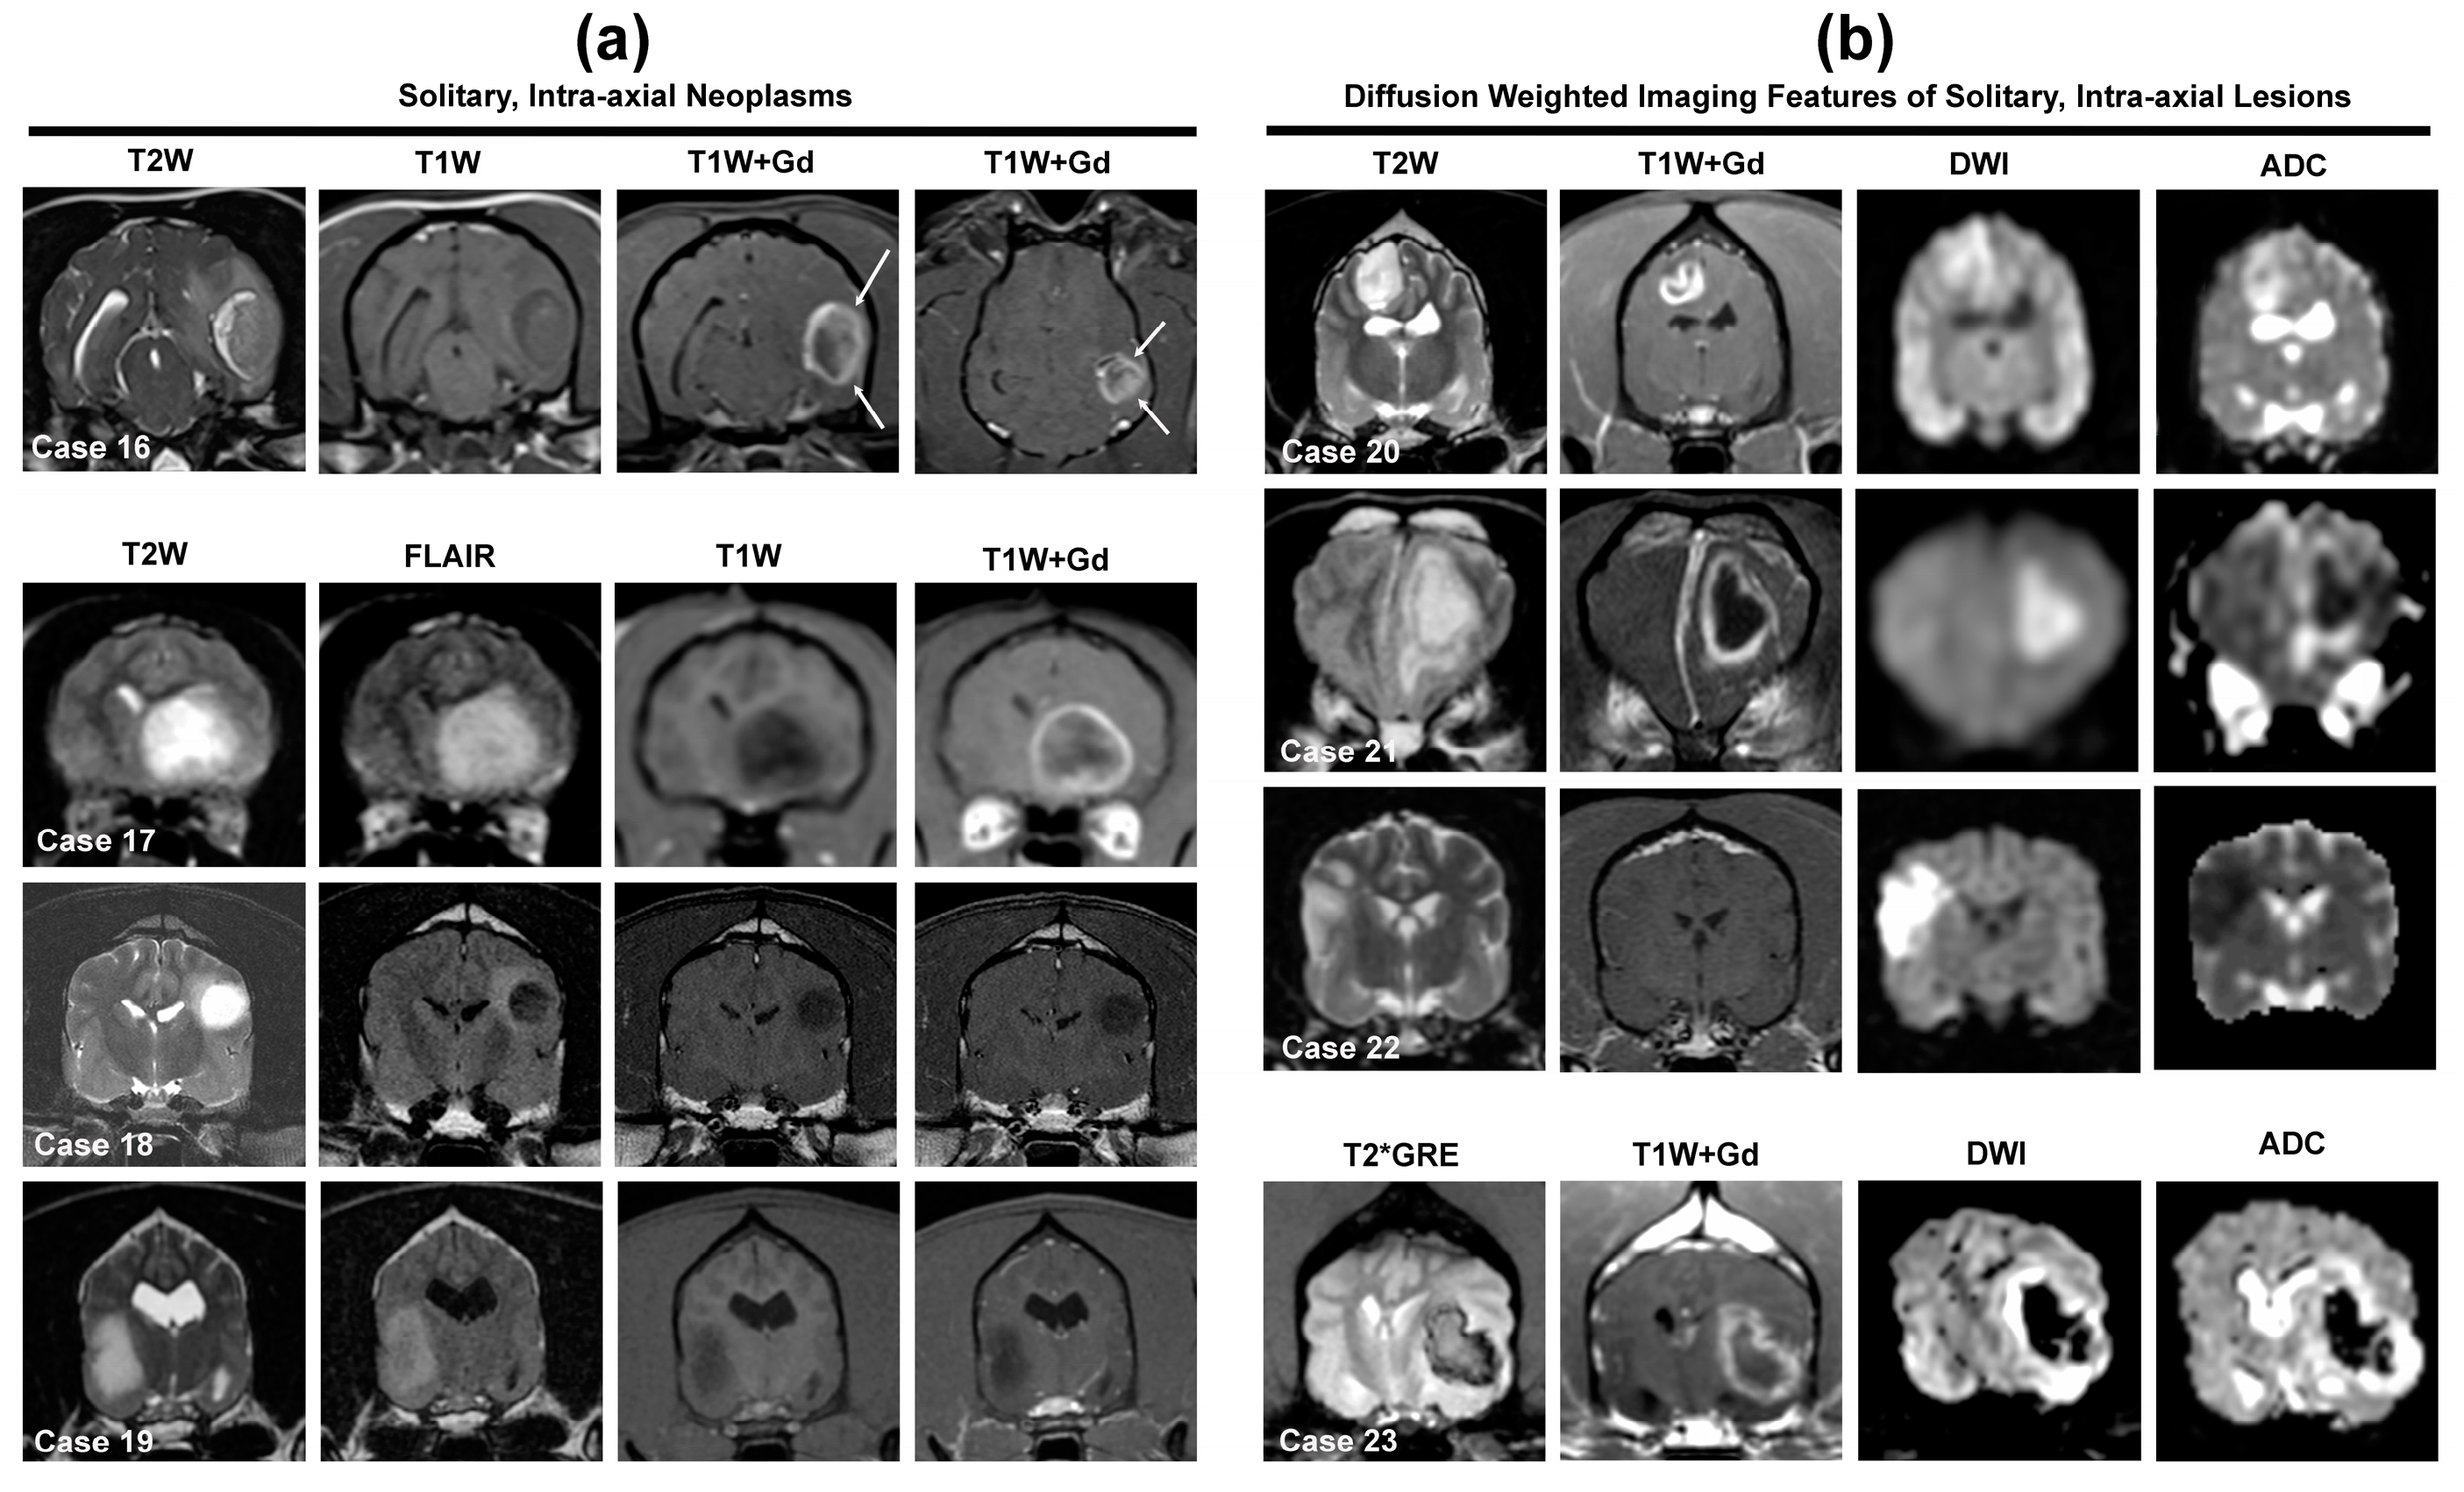

3.3. Solitary Intra-Axial Mass Lesions

3.3.1. Gliomas (Astrocytoma, Oligodendroglioma, Undefined Glioma)

3.3.2. Other Solitary Intra-Axial Tumors

3.6.1. Diffusion-Weighted Imaging